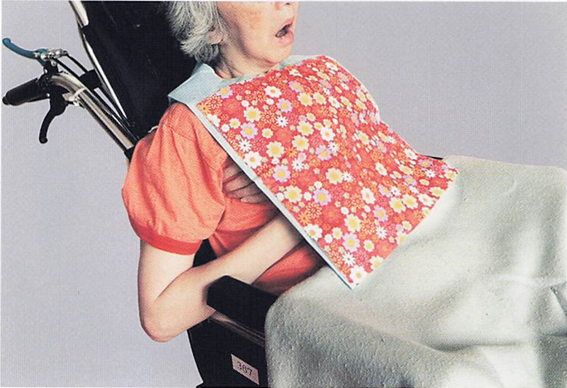

午前-59

86歳の女性。特別養護老人ホームに入居している。エプロンが気になって食事に集中しない。食事動作を中断して動かない様子がミールラウンドで 観察された。患者の写真を別に示す。 疑われるのはどれか。1つ選べ。

a.脳血管性認知症

b.前頭側頭型認知症

c.Lewy〈レビー〉小体型認知症

d.Alzheimer〈アルツハイマー〉型認知症

解答を見る

c